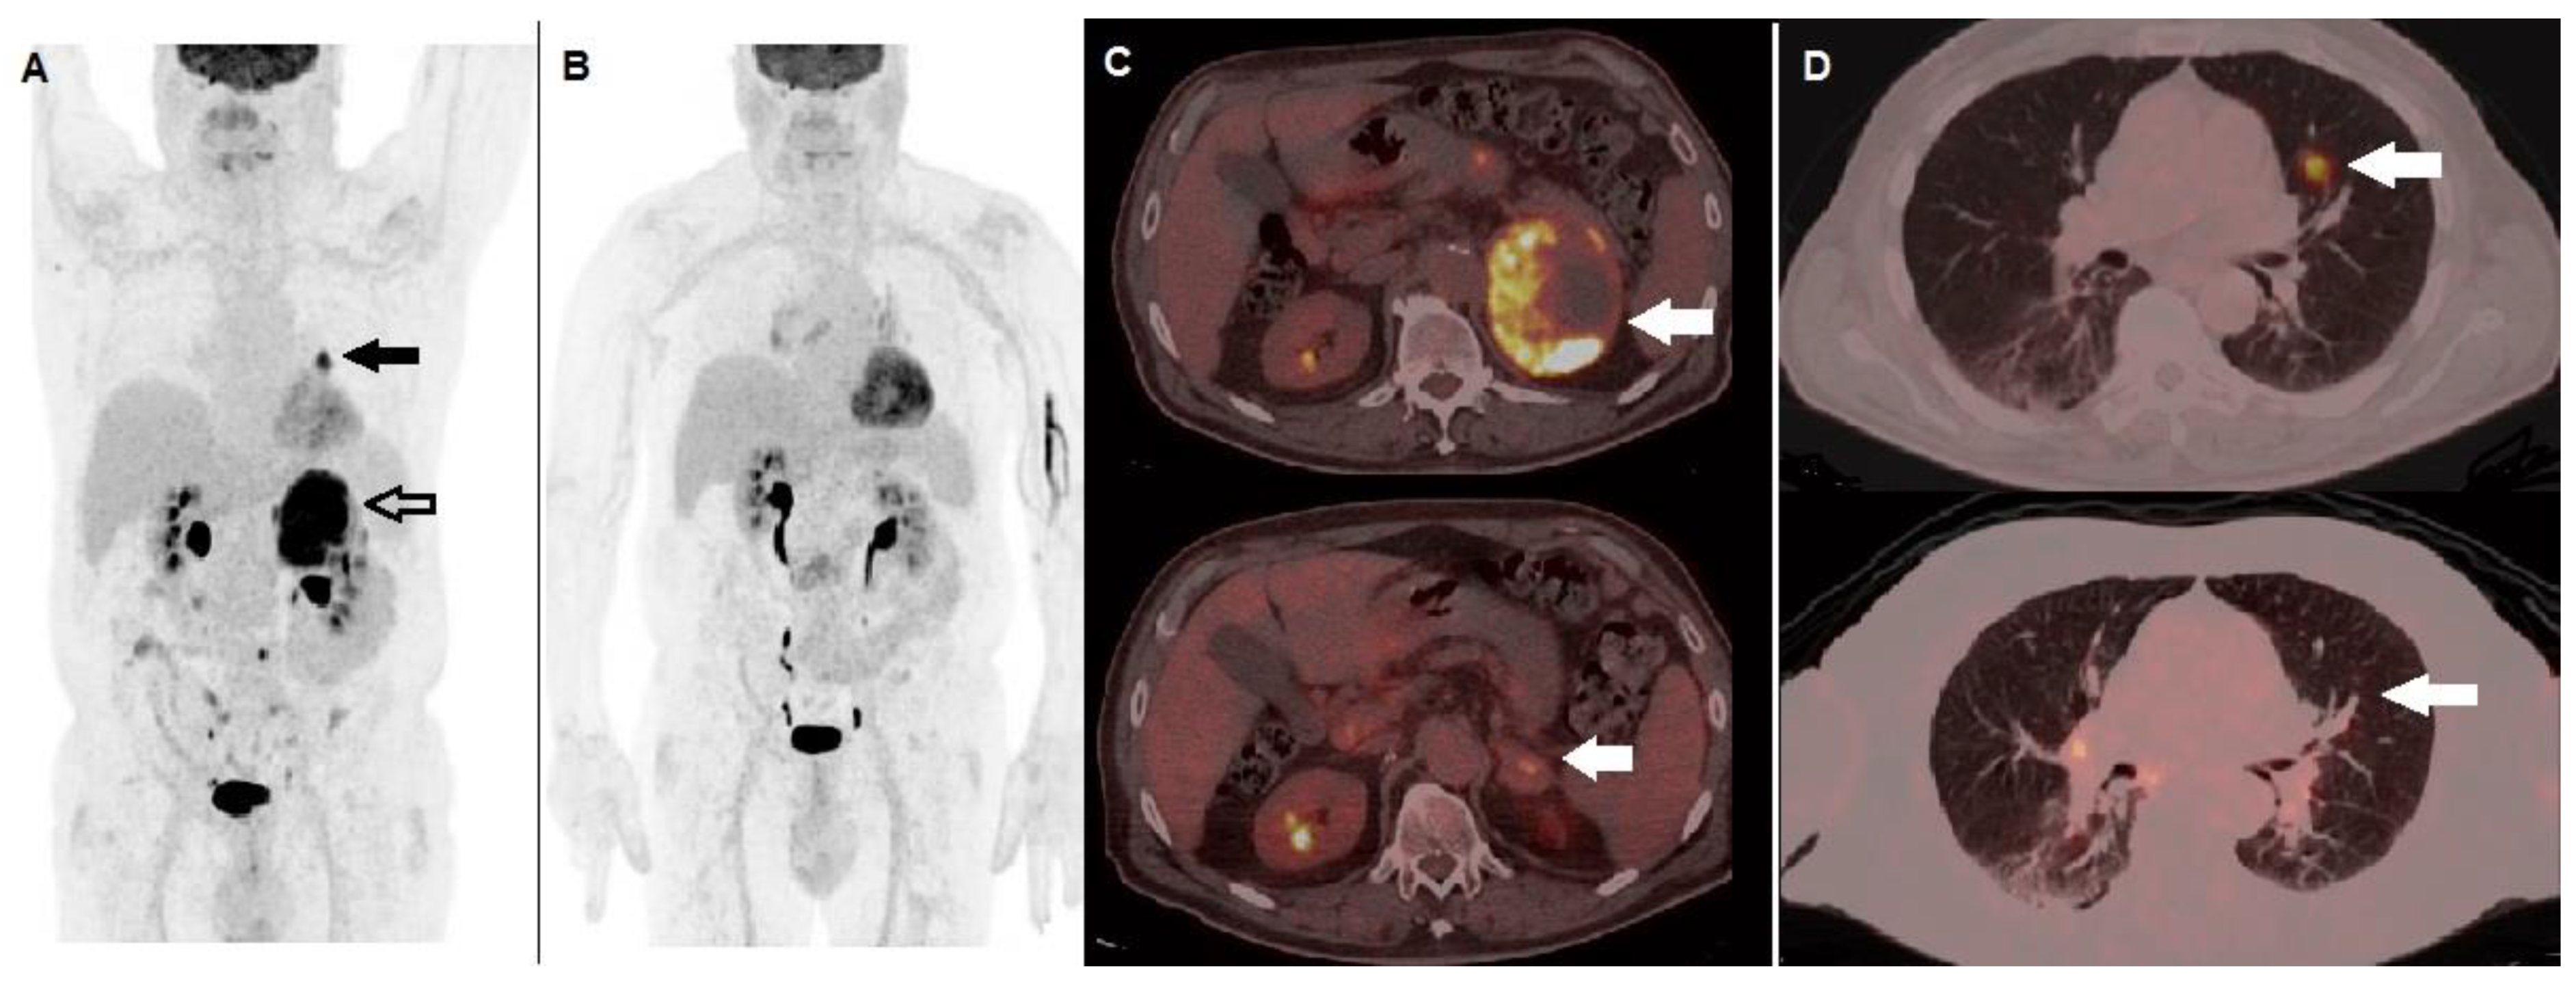

- Sachpekidis, C.; Larribere, L.; Pan, L.; Haberkorn, U.; Dimitrakopoulou-Strauss, A.; Hassel, J.C. Predictive Value of Early 18F-FDG PET/CT Studies for Treatment Response Evaluation to Ipilimumab in Metastatic Melanoma: Preliminary Results of an Ongoing Study. Eur. J. Nucl. Med. Mol. Imaging 2015, 42, 386–396. [Google Scholar] [CrossRef]

- Anwar, H.; Sachpekidis, C.; Winkler, J.; Kopp-Schneider, A.; Haberkorn, U.; Hassel, J.C.; Dimitrakopoulou-Strauss, A. Absolute Number of New Lesions on 18F-FDG PET/CT Is More Predictive of Clinical Response than SUV Changes in Metastatic Melanoma Patients Receiving Ipilimumab. Eur. J. Nucl Med. Mol. Imaging 2018, 45, 376–383. [Google Scholar] [CrossRef]

- Filippi, L.; Proietti, I.; Petrozza, V.; Bagni, O.; Schillaci, O. Cutaneous Squamous Cell Carcinoma Subjected to Anti PD-1 Immunotherapy: Monitoring Response Through Serial PET/CT Scans with 18 F-FDG. Cancer Biother. Radiopharm. 2022, 37, 226–232. [Google Scholar] [CrossRef] [PubMed]

- Ito, K.; Teng, R.; Schöder, H.; Humm, J.L.; Ni, A.; Michaud, L.; Nakajima, R.; Yamashita, R.; Wolchok, J.D.; Weber, W.A. 18F-FDG PET/CT for Monitoring of Ipilimumab Therapy in Patients with Metastatic Melanoma. J. Nucl. Med. 2019, 60, 335–341. [Google Scholar] [CrossRef] [PubMed]

- Sachpekidis, C.; Anwar, H.; Winkler, J.K.; Kopp-Schneider, A.; Larribere, L.; Haberkorn, U.; Hassel, J.C.; Dimitrakopoulou-Strauss, A. Longitudinal Studies of the 18F-FDG Kinetics after Ipilimumab Treatment in Metastatic Melanoma Patients Based on Dynamic FDG PET/CT. Cancer Immunol. Immunother. 2018, 67, 1261–1270. [Google Scholar] [CrossRef] [PubMed]

- Sachpekidis, C.; Kopp-Schneider, A.; Hakim-Meibodi, L.; Dimitrakopoulou-Strauss, A.; Hassel, J.C. 18F-FDG PET/CT Longitudinal Studies in Patients with Advanced Metastatic Melanoma for Response Evaluation of Combination Treatment with Vemurafenib and Ipilimumab. Melanoma Res. 2019, 29, 178–186. [Google Scholar] [CrossRef]